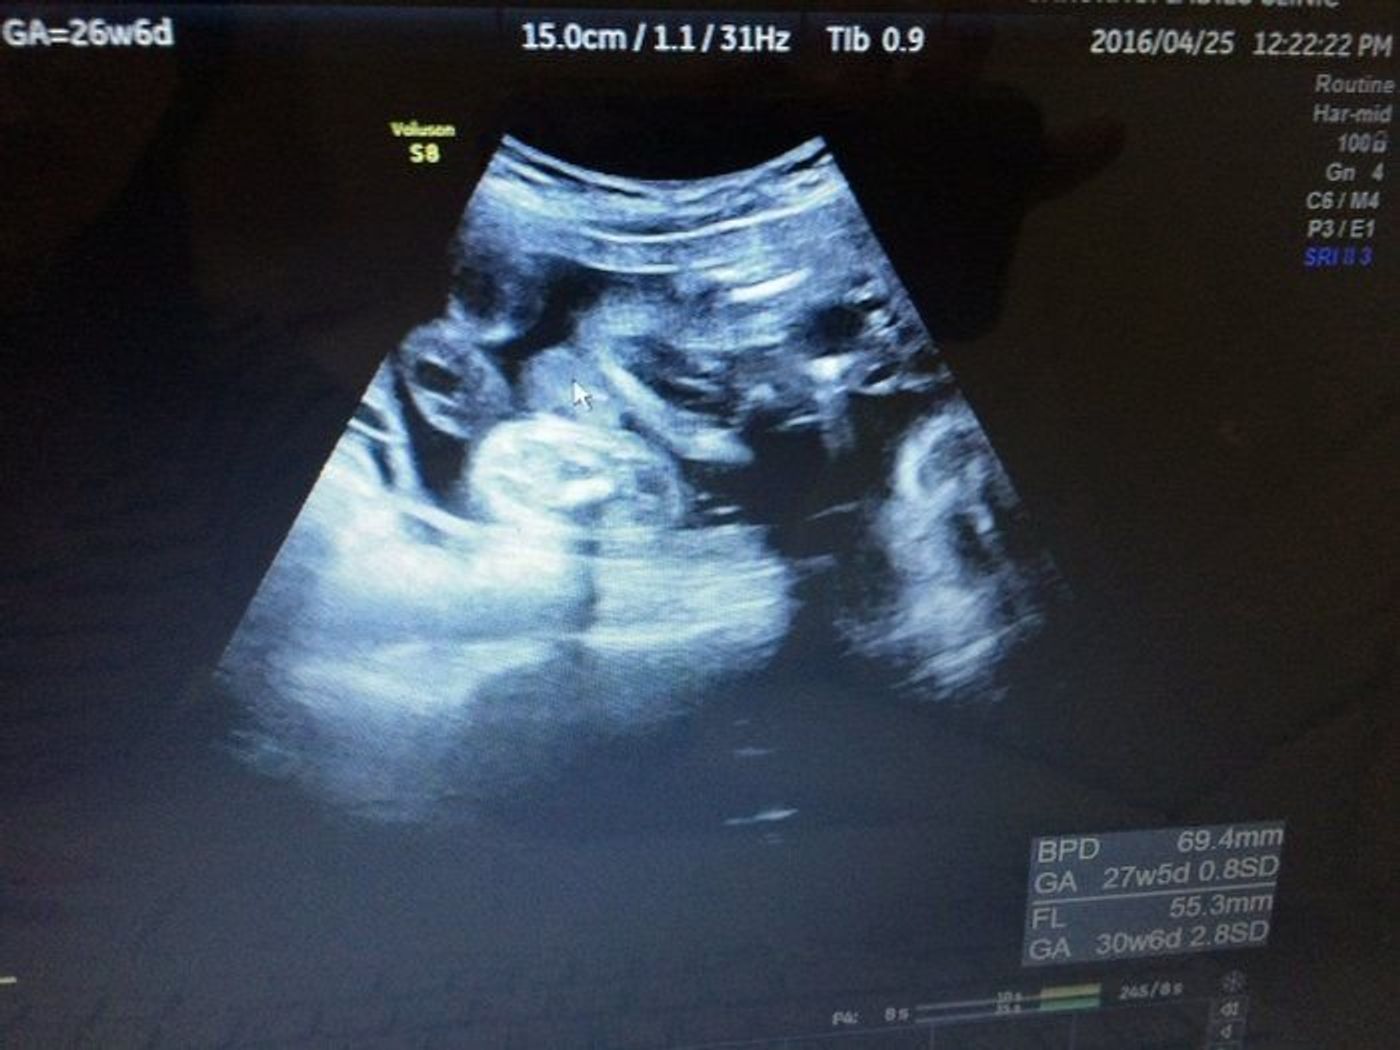

この頃になると 女の子の赤ちゃんは、子宮と膀胱が2つの黒い点となって見えます 。 一方、男の子は子宮がないため黒い点は1点のみです。

妊娠26週 赤ちゃんのエコー写真 超音波写真まとめ たまひよ

27週 性別確定 7カ月後半 中期最後の妊婦健診と性別判断の胎児のエコー写真 らくがきクリエイトmononoco

性別確定 こんばんは 妊娠中で26週になり女の子確定と言われました 避妊 教えて Goo